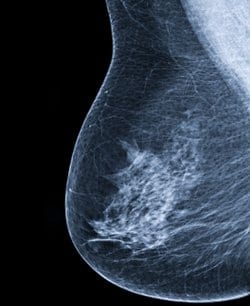

בהסתמך על 831,000 בדיקות סקר של ממוגרפיה דיגיטלית מ- 365,000 נשים (גילאים 40-74), העריכו החוקרים את הסבירות לסרטן שד המאובחן בתוך 12 חודשים מבדיקת סקר ממוגרפית שלילית, בהסתמך על צפיפות השד בלבד או בשילוב עם הסיכון להיארעות סרטן שד בתוך 5 שנים המחושבת באמצעות ה- Breast Cancer Surveillance Consortium risk model.

כמעט מחצית מכלל הנשים סווגו כבעלות רקמת שד צפופה. כמחצית מהנשים הללו הציגו סיכון מוערך נמוך עד ממוצע לסרטן שד (0%–1.66%). עבור מרבית הנשים שעברו ממוגרפיה דיגיטלית (כולל נשים עם שד צפוף אך סיכון נמוך ל- 5 שנים), שיעור היארעות הסרטן הייתה נמוכה ממקרה אחד פר 1,000.

כמחצית מכלל הנשים עם שד צפוף – כולל כל הנשים עם סיכון מוערך נמוך עד ממוצע ל- 5 שנים – לא הציגו שיעור תחלואה גבוה.